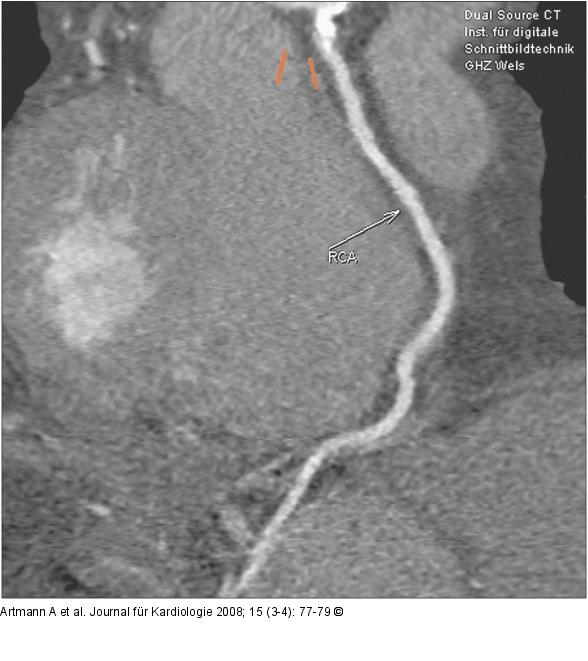

Abbildung 2: RCA RCA (right coronary artery), MPR- (Multiplanare Reformation) Darstellung. |

RCA (right coronary artery), MPR- (Multiplanare Reformation) Darstellung. |